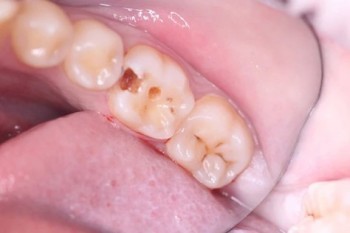

Кхалил Абаноуб Адли Абдуллах: портфолио (4)